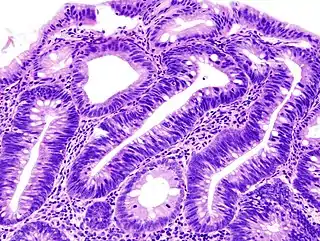

![]() Adenoma de colon | ||

- Adenoma de colon: aparece en el colon. Adquieren en la mayoría de los casos la morfología de pólipo de colon.